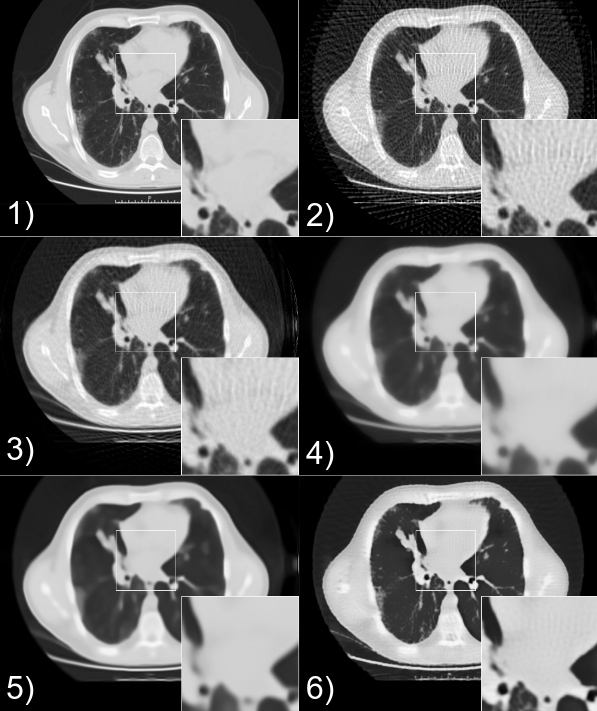

Example resuls from from this paper.

From left to right: ground truth, FBP, SART, SART+TV, SART+BM3D, the proposed method (learned self-supervised).